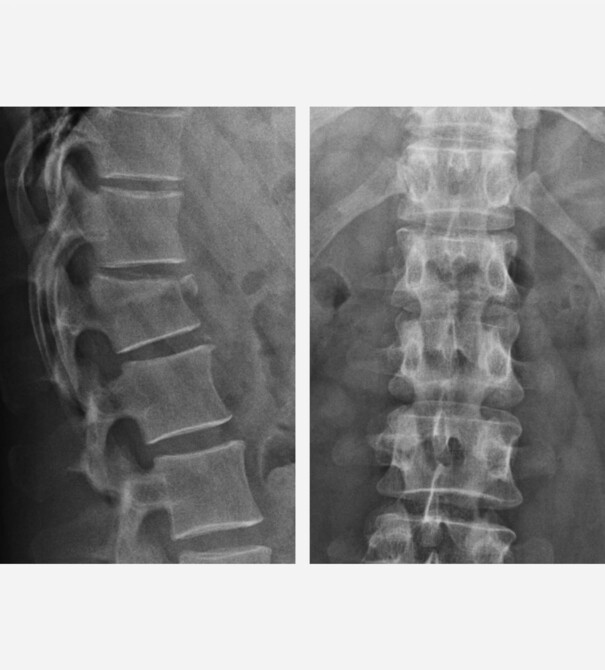

Als Leitsymptom besteht bei allen Patienten der akute Schmerz. Wenn entsprechende Risikofaktoren bestehen oder ein Unfallmechanismus stattgefunden hat, führen wir zunächst eine strahlenarme digitale Röntgenbildgebung durch. Bestätigt sich der Verdacht, ist oft noch ein ergänzendes MRT und/oder auch eine CT-Untersuchung notwendig, um das genaue Ausmaß des Bruchs festzustellen.